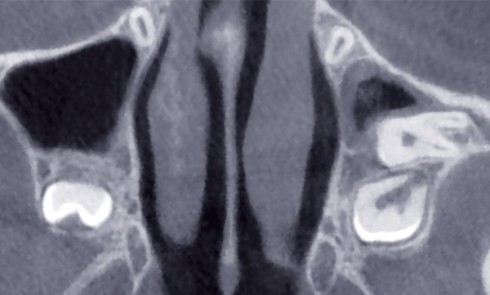

Article réservé à nos abonnés Chronologie du plan de traitement : paro, ortho, implanto

Depuis les travaux de Brånemark, l’implantologie moderne basée sur les données scientifiques offre une option thérapeutique fiable à long terme....